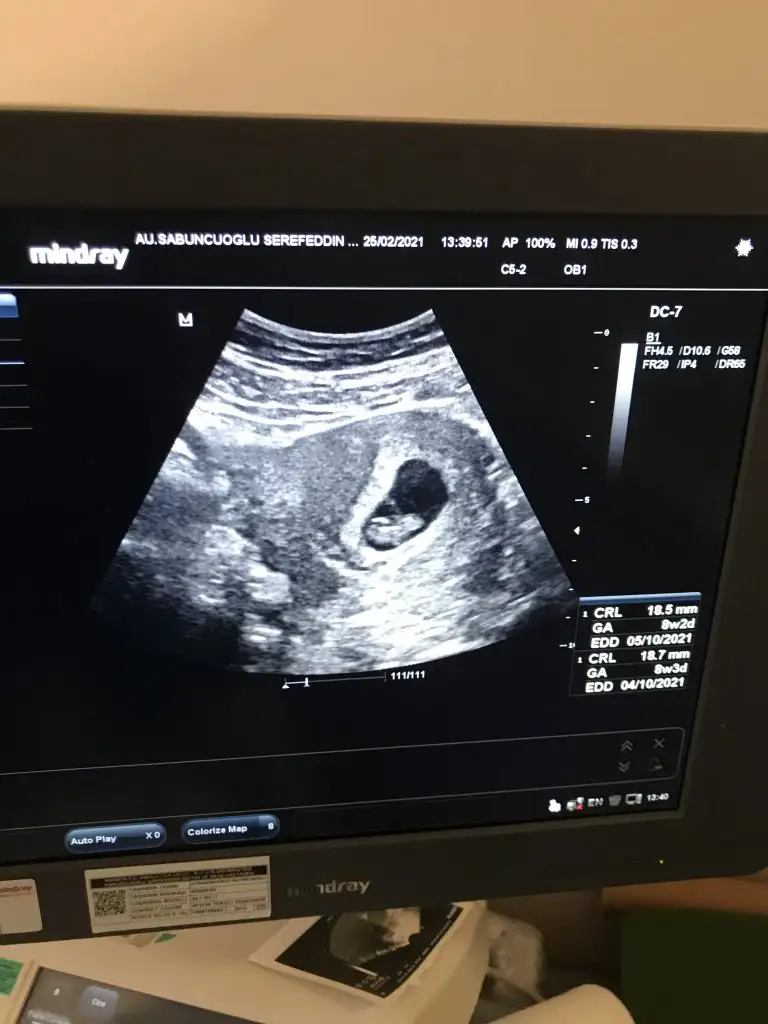

Bebeğin konumuna göre kız sanırımBi oglum var onceligimiz saglikli olmasi tabiki ama insan merak ediyor canm banada bakarmisin 8+3 karından

6-7 hafta arası varsa yorumlayabilirim ama uzman değilim öyle eğlencesineEki Görüntüle 2789978 lutfen yorum yaparmisiniz kizmi erkekmi

Sanırım kız gibi geldi banaMerhaba benim bebişin cinsiyetinide tahmin edebilir misiniz?Üzerinde haftalar yazıyor . 6 haftalık vajinadan 7 haftalık karından simdiden teşekkür ederim